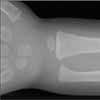

The skull, the long bones of the extremities, and the clavicle are most susceptible to injury following a seemingly insignificant accidental fall.5,6 However, these are the same bones, along with the ribs, that are fractured when a child is intentionally injured. Although serious sequelae, such as depressed skull fractures, can result from a low fall, the vast majority of children do not sustain major injury.5-8

The clinician has to also consider the possibility of non-accidental trauma in any child with any type of fracture--especially in infants younger than 1 year. Banaszkiewicz and associates19 found that abuse was underestimated in 28.4% of patients younger than 1 year who were brought to the clinician with a fracture. In addition, occult fractures are also most likely to be discovered on a skeletal survey in children of this age.21 Although leg bone fractures can occur accidentally if a child runs and falls with a twisting motion while the foot remains stationary on the floor, such fractures suggest abuse in the non-ambulatory patient.

As with skull fractures, rib fractures are of extreme concern. The distal or mid clavicle can be easily injured in an accidental fall, but a fracture of the most medial aspect of the clavicle is particularly worrisome.22 The long bones are commonly injured in an accident, but in a child older than 1 year, the long bones (femur, humerus, tibia, and forearm bones) are also the most common location of non-accidental injury.22

Imaging studies are often necessary in the assessment of an infant or young child with an obvious or suspected injury. The skeletal survey (Table 3) is recommended and is mandatory in all cases of suspected abuse in children younger than 2 years.24 However, it has little value in children older than 5 years.25 Patients between ages 2 and 5 years are assessed on an individual basis.

If clinical findings point to a specific injury site, that anatomic region should be evaluated with a radiograph--regardless of the child's age.25 An experienced radiologist should be present while imaging is performed to ensure that high-resolution images of good quality are obtained. If the initial skeletal survey is unremarkable but abuse is still strongly suspected, a repeated skeletal survey in 2 weeks may offer greater yield in discovering occult fractures.26 A bone scan is another option for searching for occult fractures: the need for this modality is determined on a case-by-case basis.